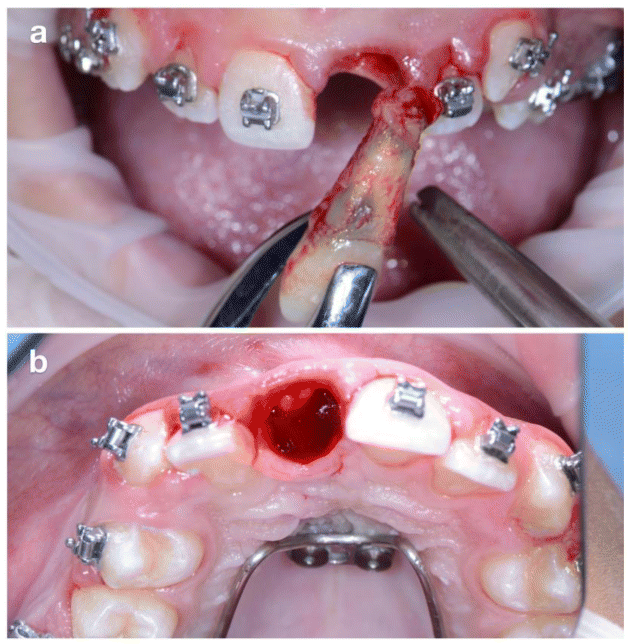

The donor tooth chosen was the maxillary left second premolar (2.5), which presented incomplete root development (Figure 3b). Following six weeks of orthodontic pre-treatment to mobilize and stimulate periodontal tissues (Figure 3), surgical extraction of 2.1 was performed under local anesthesia (Figure 4).

The socket was prepared using implant drills according to the dimensions of the donor tooth (Figure 5a). Tooth 2.5 was atraumatically explanted, immediately transplanted into the 2.1 site (Figure 5b), and stabilized passively with a flexible orthodontic splint. Coronoplasty was performed to avoid occlusal interference.